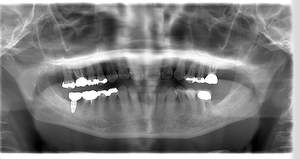

レントゲン写真

- Befor

- After

| 治療方針 | 左上7番は昔他院で被せものをしており、被せものの中が歯ぐきの中まで虫歯になっていたため抜歯せざるを得ない状態だった。抜歯と同時に骨造成を行い、骨が出来るまで4ヵ月待ってからインプラントを埋入した。 ※2ポンティック・・・歯のない部分を補うダミーの歯。 |

| 担当者所見 | 元々金属の被せものが多く入っていたため、2次カリエス※3が多かった。今回は金属ではなく、ジルコニアを使用し、2次カリエスにならないよう、患者様にはブラッシング指導とメンテナンスの重要性をお伝えした。 ※3二次カリエス・・・詰め物や被せものを入れた歯が虫歯になること。 |